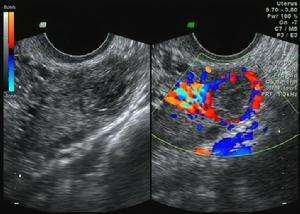

2.体征 肌壁间肌瘤子宫增大 ,表面不规则,单个或多个结节状突起,质硬; 浆膜下肌瘤可扪及质硬、球状物与子宫相连; 粘膜下肌瘤子宫多为均匀增大,有时宫颈口扩张,肌瘤位于宫颈口内或脱出在阴道内呈红色、实性、光滑,若伴感染,表面有渗出液覆盖或溃疡形成,排液有臭味。也可通过B超、腹腔镜及宫腔镜进行辅助检查。